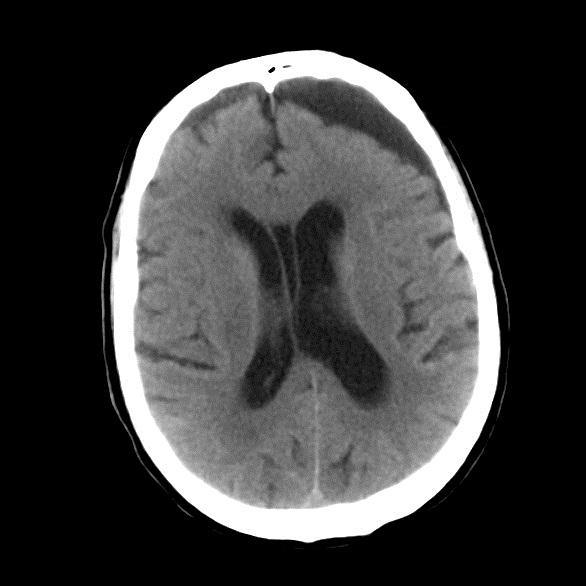

Multiple Brain Mets

Il y a 7 ans